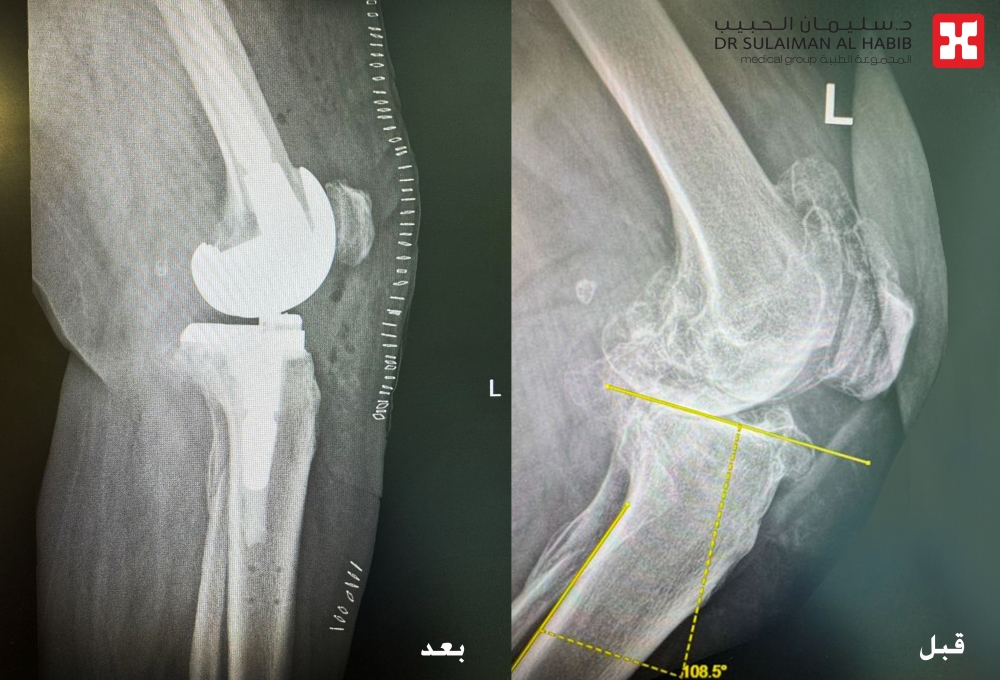

وأظهرت النتائج وجود خشونة شديدة من الدرجة الرابعة، وهي أعلى درجات تآكل المفصل، مع احتكاك مباشر في العظام، وتآكل بالغضاريف المحيطة بالركبة، وتكوّن تكلسات خلف المفصل، فضلًا عن وجود انحراف وتقوّس واضح في شكل الركبة. هذه المعطيات أكدت أن العلاج التحفظي لم يعد مجديًا، وأن التدخل الجراحي أصبح الخيار الأنسب لاستعادة الحركة وتخفيف الألم.

يقوم الروبوت الجراحي برفع القياسات بدقة متناهية، وتحديد مواضع القطع الجراحي وزواياه، واختيار المفصل الصناعي الأنسب لحالة المريض، بما يضمن أعلى مستويات التوافق بين المفصل الصناعي وبنية الركبة الطبيعية. هذه الدقة تقلل من هامش الخطأ البشري إلى أدنى مستوى، وتضمن توزيعًا مثاليًا للحركة والضغط داخل المفصل بعد الزراعة.

كما تم خلال العملية تصحيح الانحراف والتقوس في الركبة باستخدام دعامة متطورة تشمل الساق والفخذ، ما أسهم في استعادة المحور الطبيعي للطرف السفلي وتحقيق توازن أفضل أثناء المشي.